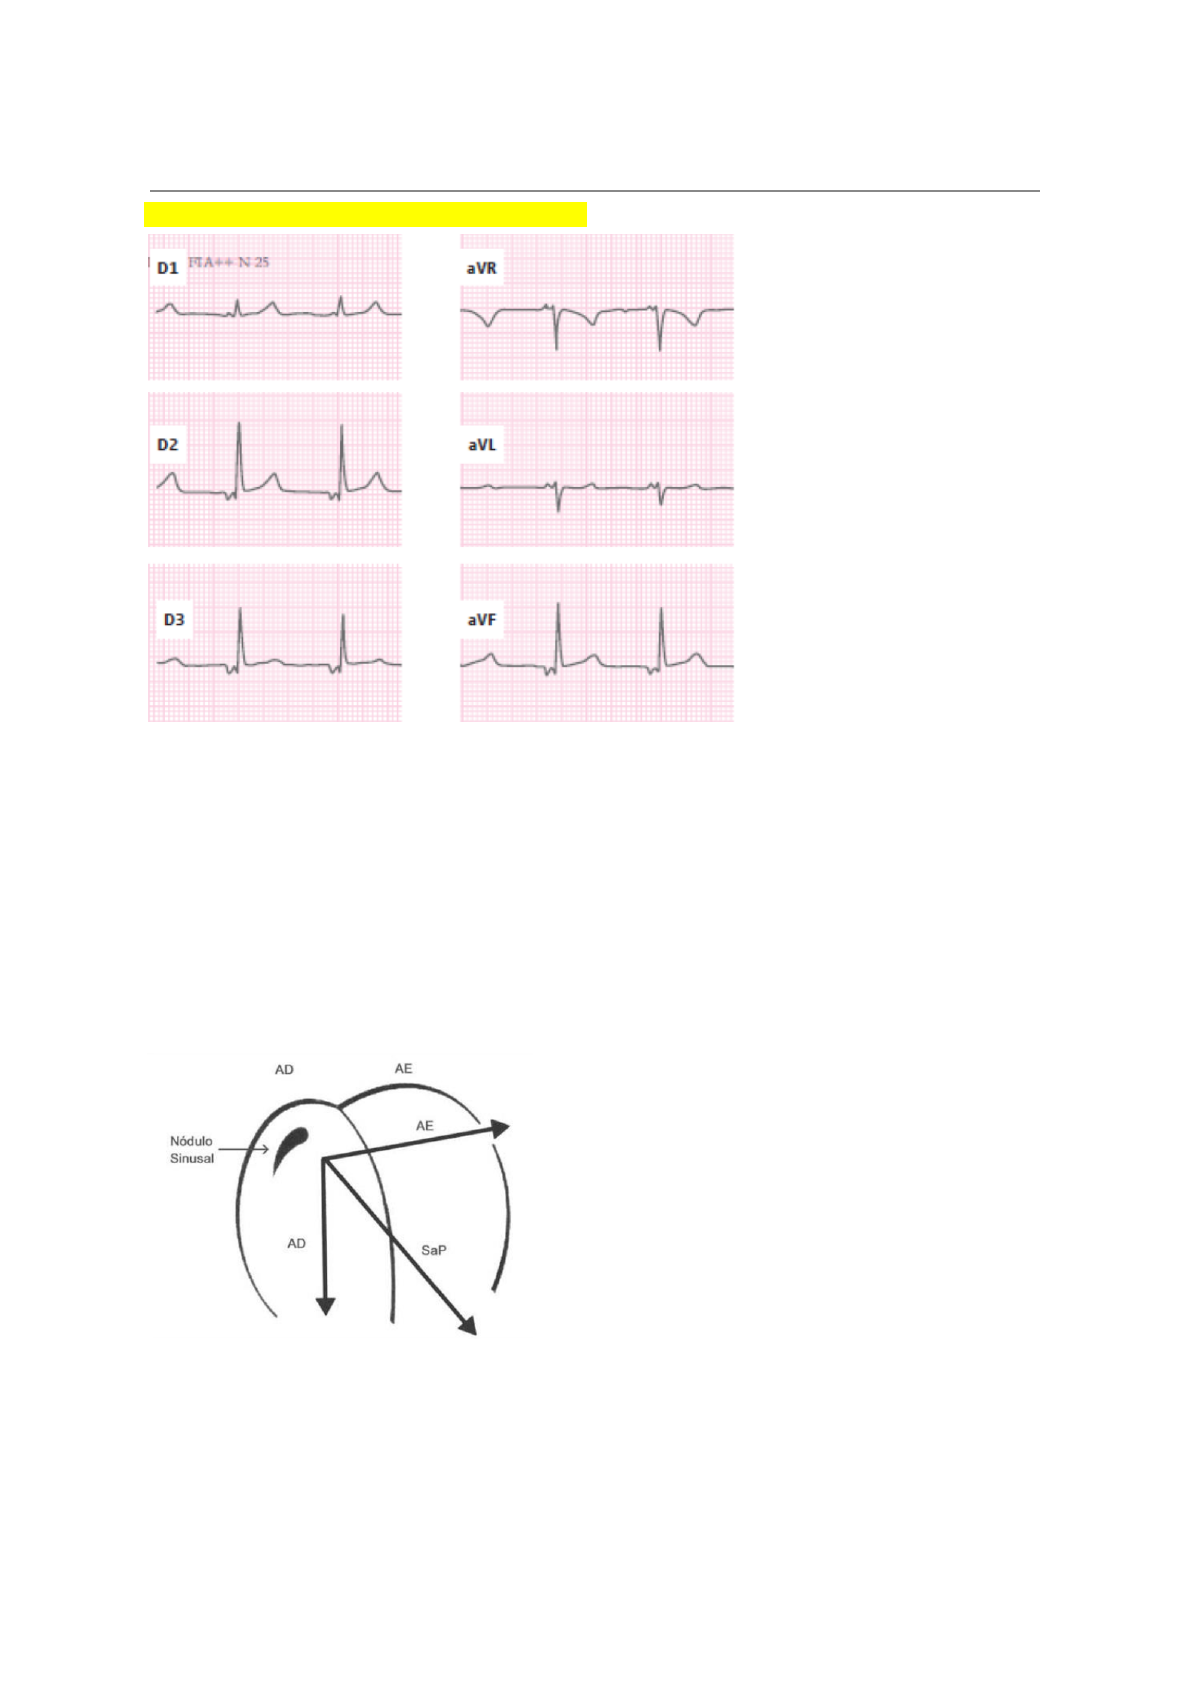

Onda P apresentando ritmo atrial ectópico

Lembre-se que é um ritmo sinusal quando a onda P:

1. Existe

2. Precede o QRS

3. É positiva em D1, D2 e avF (ou em pelo menos duas dessas 3 derivações)

A onda P, nesse caso, não é positiva em D2 e avF, portanto não se trata de um ritmo sinusal

– a onda P nesse caso é muito pequena e fica imediatamente antes do QRS (a onda maior

que aparece no início do traçado é a onda T!).

As ondas P estão negativa porque estão acontecendo de baixo para cima, sentido oposto

do usual, que deveria ser como na imagem abaixo:

Para a esquerda (D1), oblíqua para a esquerda (D2) e para baixo (avF).